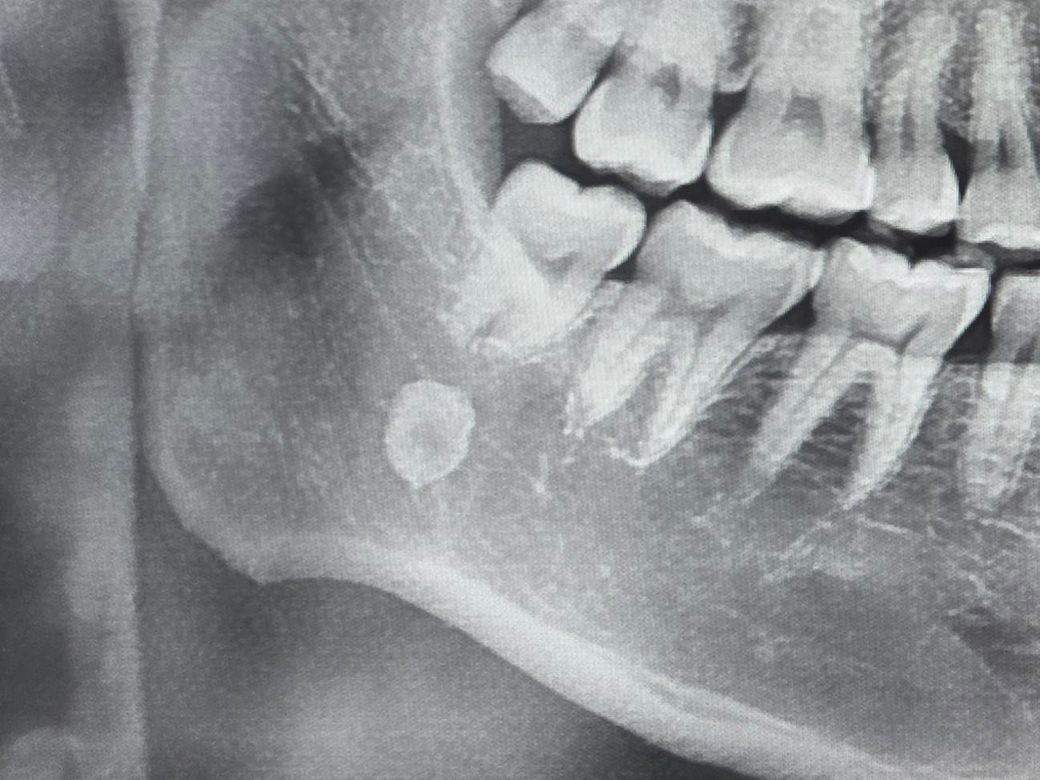

첨부한 엑스레이 사진을 보면 턱부위에 뼈로 보이는 것이 관찰됩니다

무엇인지 왜그런건지 진료를 받아봐야 되는건지 궁금합니다,,

사진에서 턱 아래 보이는 하얀 구조는 위치에 따라 하얀 구조는 위치에 따라 "설골"이나 턱 주변 정상 뼈 구조로

보이는 경우가 흔합니다.

또 일부에서는 침샘관에 생기는 "타석증(침샘 돌)이나 석회화가 X-ray에 보이기도 합니다.

통증, 턱 움직임 제한, 붓기 같은 증상이 없다면 우연히 보이는 정상 구조일 가능성도 있습니다.

그래도 정확한 확인을 위해 "치과" 또는 "구강악안면외과"에서 판독 상담을 받아보세요.

엑스레이상 보이는 턱뼈 안쪽의 동그란 음영은 골경화증을 가능성이 가장 흔하며 통증이 없다면 대부분 치료할 필요가 없으며 정기적으로 관찰만 하는 경우가 대부분 입니다.

특발성 공경화증과 같은 뼈의 밀도가 국소적으로 높아져 방사선 사진상 하얗게 나타나는 현상입니다. 구체적인 원인은 밝혀지지 않았지만 자연스러운 뼈 변화나 과거의 미세한 자극에 대한 반응으로 추측됩니다. 일반적으로 치료가 필요없는 경우가 대부분이지만 매복치,치아종 처럼 다른질환들일수 있어 정확한 감별이 필요합니다. 안심하시되 혹시모르니 치과에 방문하셔서 정확한 확인을 해보는걸 추천드립니다. 감사합니다!

반드시 뼈와 같은 구조물이라 보이기 보다는 촬영각도나 겹쳐보이는 경우나 주변 연부조직에 발생하는 석회화등일 수 있지만 단적인 촬영본 만으로는 정확한 원인을 특정하기 어려울 수 있으므로, 통증이나 불편감이 동반되어서 나타나는 경우에는 병원에서 진료를 통해 정확한 원인을 파악하시는 것을 추천드립니다.